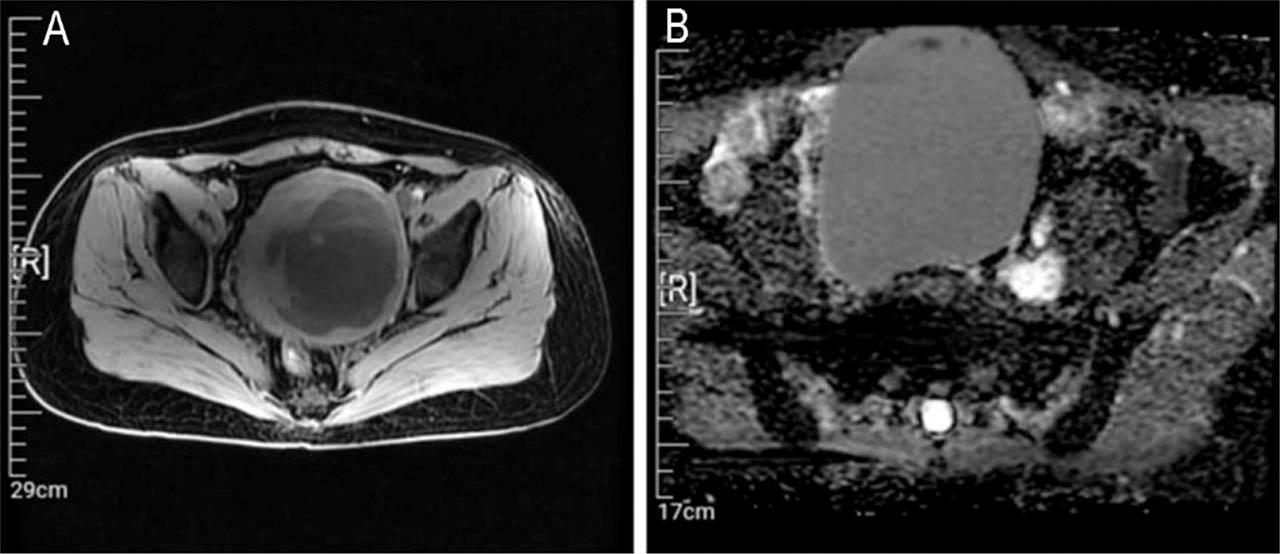

Figure 2

Magnetic resonance imaging and macroscopic findings. (A) T2-weighted image and (B) diffusion-weighted image depicting a high signal intensity in the uterine fibroid.